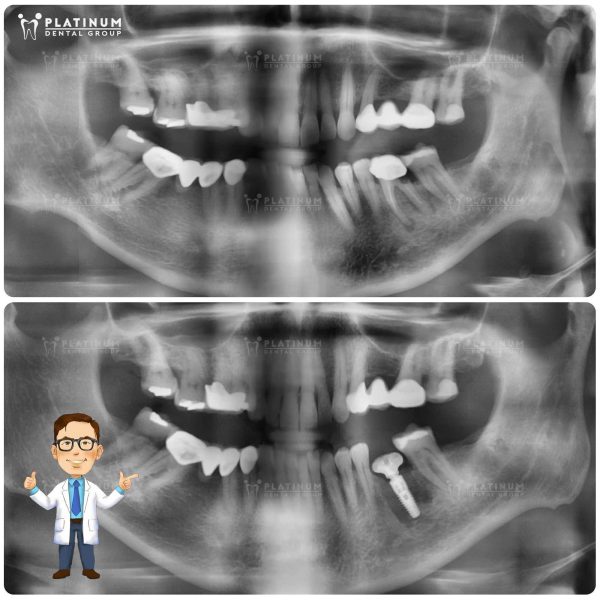

Khi răng khôn mọc lệch – “Thủ phạm” âm thầm làm mất răng bên cạnh

Không phải ai cũng biết rằng, răng khôn mọc sai hướng không chỉ gây đau nhức tạm thời mà còn có thể là nguyên nhân dẫn đến mất răng vĩnh viễn. Trường hợp bệnh nhân này là một minh chứng điển hình: phim X-quang cho thấy răng khôn hàm dưới bên trái mọc lệch ngang, đâm trực tiếp vào chân răng số 7 bên cạnh. Áp lực kéo dài âm thầm khiến răng khôn bị tiêu xương vùng xa, sâu nặng ở chân răng và cuối cùng không còn đủ điều kiện để giữ lại.

Trước mức độ tổn thương không thể hồi phục, ThS, BS CKII Dương Minh Tùng đã chỉ định nhổ bỏ cả hai răng, đồng thời tiến hành cấy Implant tại vị trí răng số 7 nhằm phục hồi chức năng nhai cho bệnh nhân. Giải pháp này không chỉ đảm bảo lực nhai bền vững như răng thật, mà còn giúp bảo tồn cấu trúc xương hàm, ngăn ngừa tiêu xương trong tương lai, điều mà cầu răng hay hàm tháo lắp không thể làm được. Đây là lý do vì sao Implant luôn là lựa chọn ưu tiên trong các trường hợp mất răng hàm quan trọng.